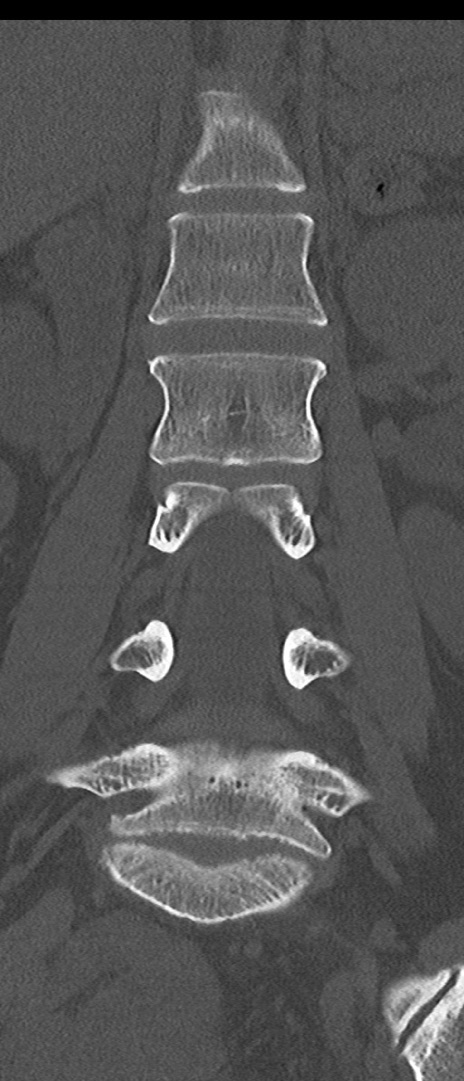

【整形】TIPS症例4 腰椎CT(冠状断像)

腰椎CT

矢状断像